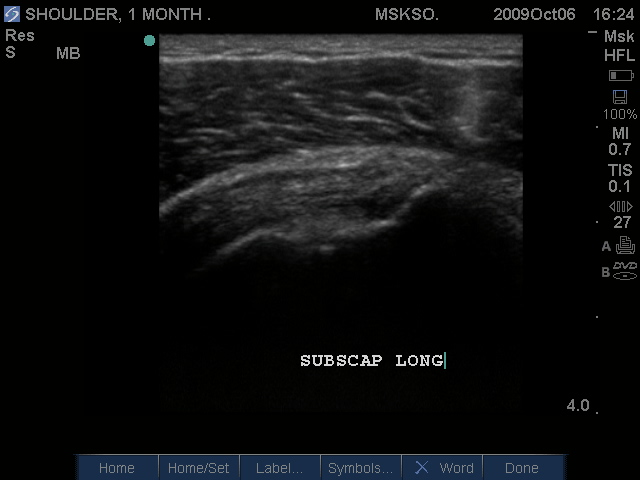

Long axis Subscapularis tendon inferior margin; articular surface partial tear

Long axis (left) and Transverse (right) images of Subscapularis Tear